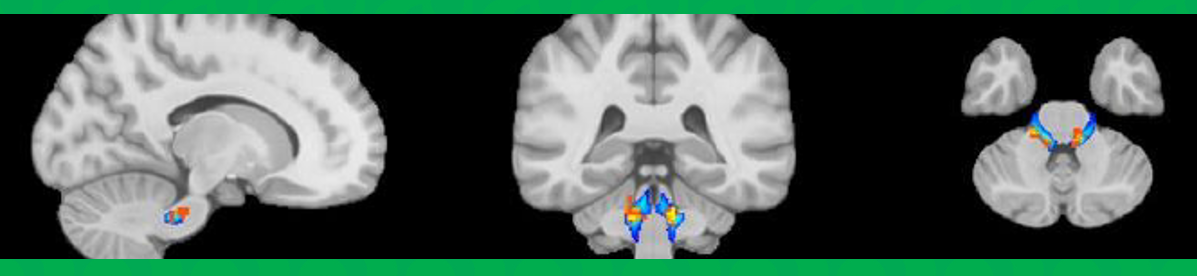

Results

Picture1

Figure 1. PRE > MID. Paired grey matter (GM) CVR difference map expressed in t-values (paired t-test; n=16; p<0.05). Significant decreases in CVR are shown in the left putamen and bilaterally in the cingulate and paracingulate gyrus. Images are in MNI space.

Figure 2. Average (A) PRE (n=18), (B) MID (n=18), and (C) POST (n=16) GM CBF expressed in mL/100g/min. Images are in MNI space.

• Our results demonstrate that nonconcussive head impacts may lead to decreased CVR and possibly increased CBF, suggesting vascular dysfunction2 and compensatory hyperemia7